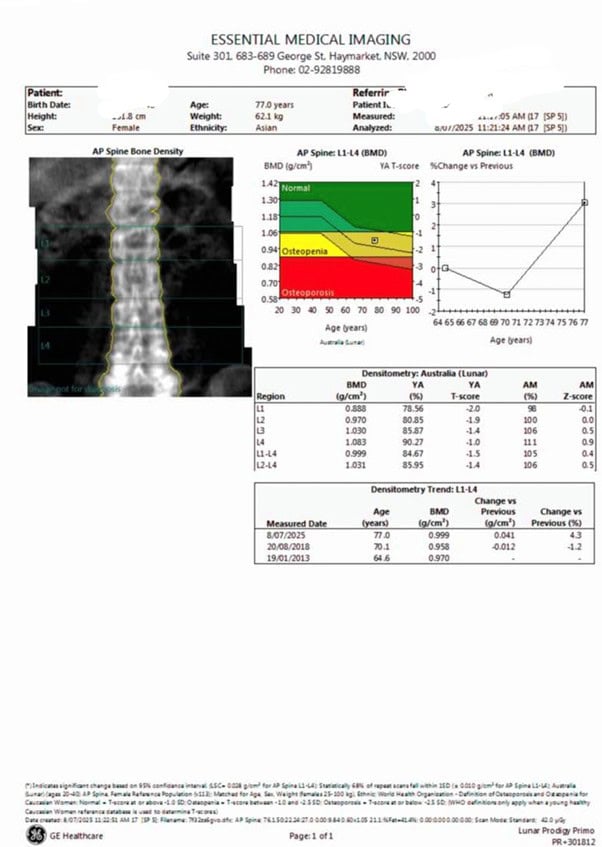

最近看了兩例肋骨骨折的病例。一個是77歲的女士,她只是在家彎腰搞清潔,左胸脅壓在櫃子上,馬上覺得劇痛,去醫院急診,經CT檢查診斷為左第7、8肋骨骨折,再作骨質掃描,有骨質疏鬆,怪不得只是自身重力的擠壓也造成了肋骨骨折。